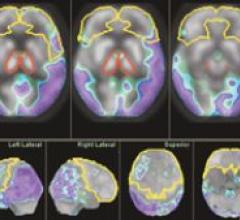

April 5, 2007 - Merge Healthcare today announced the release of its Merge PET/CT Workstation software, a vendor-neutral ...